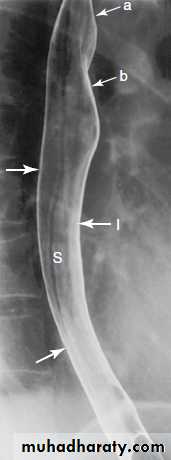

Normal appearance of the small bowel

• The normal SB occupies the central & lower abdomen.• The terminal ileum enters the medial aspect of the cecum through the ileocecal valve.

• Normal mucosa exhibit a feathery appearance [Valvulae conniventes].

• The diameter of SB loop should not exceeds 3 cm .

• Jejunum is wider than the ileum.

• Valvulae conniventes is conspicuous at jejunum more than the ileum.